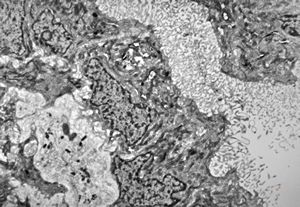

M,10y. | herpetic encephalitis